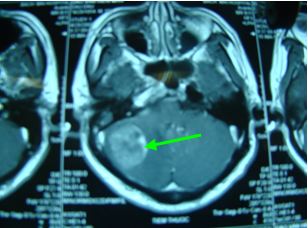

Chụp cộng hưởng từ sọ não

Kết quả: xuất hiện 1 khối tổn thương dạng thứ phát vùng bán cầu tiểu não phải kích thước 32x33mm, phù não quanh khối.

Chụp MRI sọ não

Trước điều trị: Xuất hiện 1 khối tổn thương dạng thứ phát vùng bán cầu tiểu não phải, kích thước 32x33mm, phù não quanh khối

Sau điều trị: Khối tổn thương dạng kén dịch vùng bán cầu tiểu não phải, kích thước thu nhỏ còn 14x12mm, không có phù não xung quanh